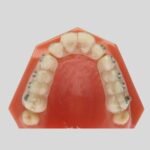

Indirect bonding

Precise bonding protocol for efficient treatment outcomes. Indirect bonding planning using orhtoanalyzer software